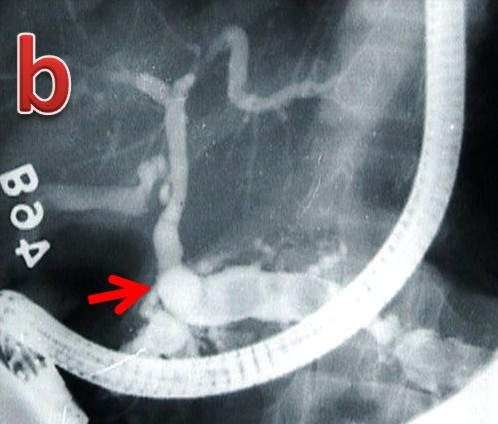

|

Figure 5. Tropical calcific pancreatitis. a. ERCP image showing a grossly dilated pancreatic duct with filling defects in the side branches and a dilated bile duct joining it in the pancreatic neck region (arrow) to form anomalous pancreaticobiliary ductal union of the B-P type. b. ERCP image showing a grossly dilated pancreatic duct with multiple large filling defects and the bile duct joining it in the body region (arrow) to form anomalous pancreaticobiliary ductal union of the B-P type. c. ERCP image showing a grossly dilated pancreatic duct with filling defects in the side branches and the bile duct joining it in the distal body region (arrow) to form a very long anomalous pancreaticobiliary ductal union of the B-P type. |